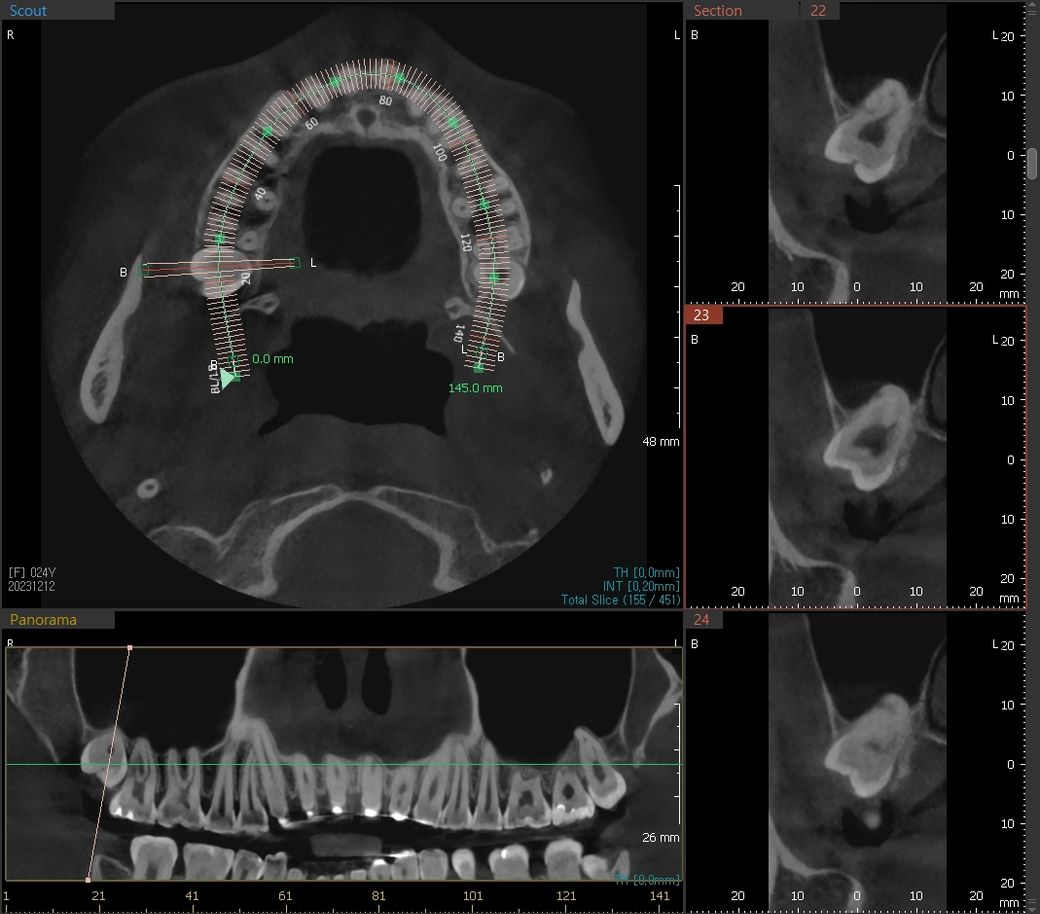

제 왼쪽 아래 매복사랑니 신경과 많이 가까운가요? 발치 시 신경손상의 가능성이 큰 편인지 궁금합니다

왼쪽 아래 매복사랑니가 신경과 가까워서 발치 시 신경손상 가능성이 좀 있다고 말씀하시던데

제 왼쪽 매복사랑니가 신경이랑 얼마나 가까운 건지,

신경 손상의 가능성이 다른 치아에 비해 정말 비교적 큰 편인지... 알고 싶습니다.

왼쪽 아래 사랑니가 깊이 매복되어 밑으로 지나가는 신경관과 사랑니 뿌리가 맞닿아 있습니다. 이런 경우 사랑니 발치후 입술이나 혀 감각이상이 오는 신경관 손상이 올 확률이 높습니다. 그렇지만 매복 사랑니 그냥두면 바로옆 어금니 상하게 하니 위험부담 앉고 발치하는 것을 추천합니다. 신경관 손상 안 올 수도 있습니다.

사진으로 봤을 경우에는 매우 깊이 있는 사랑니 이며 발치를 하면서 신경손상이 될 가능성이 높아 보입니다.

파노 상으로는 가까워 보이지만 CT상으로 보면 사랑니와 신경관과의 거리가 잇어 보입니다. 크게 걱정은 하지 않으셔도 될것같습니다. 단, 대학병원에서 발치를 하시는게 좋을것같습니다.